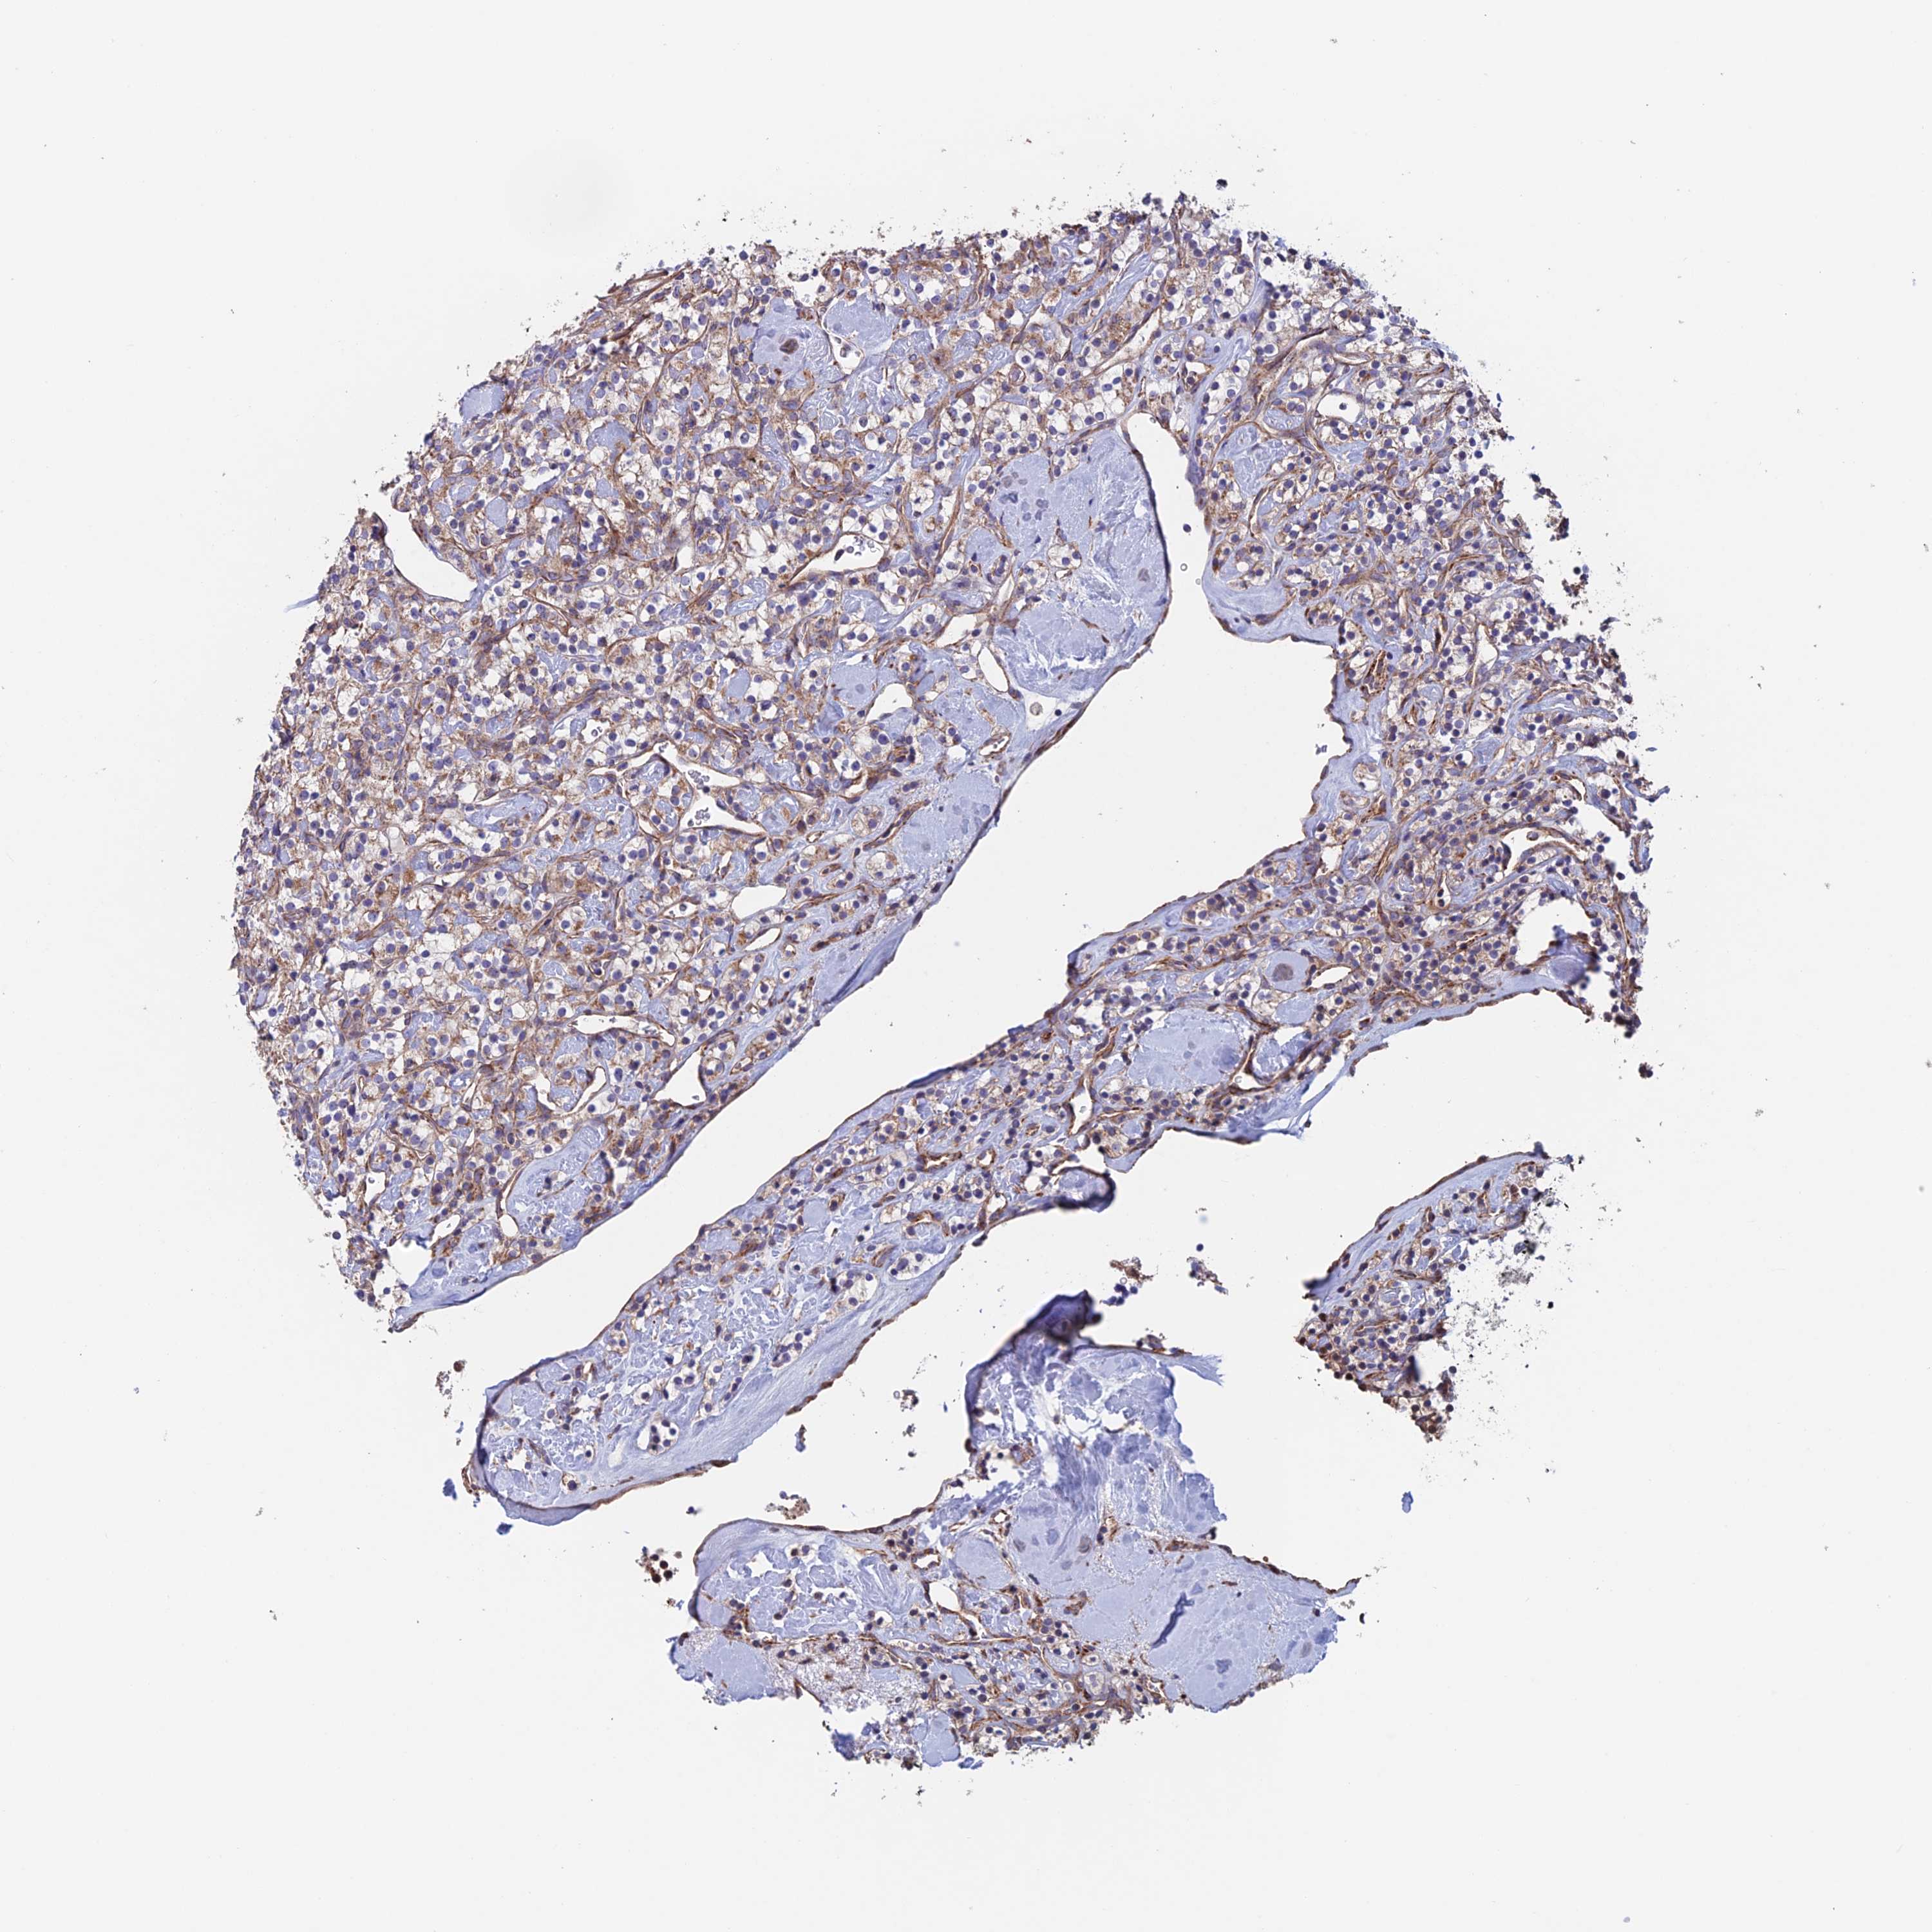

KIDNEY RENAL CLEAR CELL CARCINOMA (VALIDATION) - Interactive survival scatter ploti

The Survival Scatter plot shows the clinical status (i.e. dead or alive) for all individuals in the patient cohort, based on the same data that underlies the corresponding Kaplan-Meier plots. Patients that are alive at last time for follow-up are shown in blue and patients who have died during the study are shown in red.

The x-axis shows the expression levels (FPKM) of the investigated gene in the tumor tissue at the time of diagnosis. The y-axis shows the follow-up time after diagnosis (years). Both axes are complimented with kernel density curves demonstrating the data density over the axes. The top density plot shows the expression levels (FPKM) distribution among dead (red) and alive patients (blue). The right density plot shows the data density of the survived years of dead patients with high and low expression levels respectively, stratified using the cutoff indicated by the vertical dashed line through the Survival Scatter plot. This cutoff is automatically defined based on the FPKM cutoff that minimizes the p-score. The cutoff can be changed by dragging the vertical line or by entering a cutoff value in the square labeled "Current cut-off".

Under the Survival Scatter plot the p-score landscape (black curve; left axis) is shown together with dead median separation (red curve; right axis). Dead median separation is the difference in median mRNA expression between patients who have died with high and low expression, respectively. It is calculated as follows: median FPKM expression of dead patients with high expression - median FPKM expression of dead patients with low expression. This is intended to aid the user in visually exploring custom cutoffs and the associated p-scores and dead median separation.

Individual patient data is displayed and can be filtered by clicking on one or more of the category buttons on the top of the page. Categories describing expression level and patient information include: high, low, alive, dead, female, male and tumor stages. The scale of the x-axis can be toggled between linear and log-scale by clicking on the "x log" button. Mouse-over function shows TCGA ID, patient information and mRNA expression (FPKM) for each patient.

& Survival analysisi

Kaplan-Meier plots summarize results from analysis of correlation between mRNA expression level and patient survival. Patients were divided based on level of expression into one of the two groups "low" (under cut off) or "high" (over cut off). X-axis shows time for survival (years) and y-axis shows the probability of survival, where 1.0 corresponds to 100 percent.

MRPL1 is not prognostic in Kidney Renal Clear Cell Carcinoma (validation)

Best expression cut offi

Based on the FPKM value of each gene, patients were classified into two groups and association between prognosis (survival) and gene expression (FPKM) was examined. The best expression cut-off refers the FPKM value that yields maximal difference with regard to survival between the two groups at the lowest log-rank P-value. Best expression cut-off was selected based on survival analysis .

When clicking on this number, the vertical dashed line indicating cut-off, the interactive survival plot, and the Kaplan-Meier curve will be adjusted to show results based on the best expression cut-off.

: 27.55

TCGA RNA samplesi

RNA-seq data is reported as average FPKM (number Fragments Per Kilobase of exon per Million reads), generated by the The Cancer Genome Atlas (TCGA) .

Normal distribution across the dataset is visualized with box plots, shown as median and 25th and 75th percentiles. Points are displayed as outliers if they are above or below 1.5 times the interquartile range. FPKM values of the individual samples are presented next to the box plot.

Average pTPM 27.4

Number of samples 100